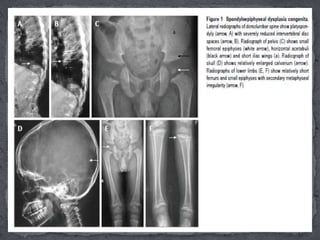

Essential radiographicfeatures:  (1)Bulbous and pear-shaped vertebrae at birth which later flatten leading to severe platyspondyly with thin intervertebral disc spaces.  The ensuing complications include kyphoscoliosis, lumbar lordosis and atlanto-axial instability. Atlanto-axial instability is secondary to odontoid hypoplasia and it subsequently endows a greatly increased risk of cervical myelopathy.  (2) Absent pubic bones at birth with horizontal roofs of acetabula and short and broad iliac wings;  (3) Absent epiphyses of calcaneum and knee at birth. Later, there’s delay in the ossification of the heads of femur  While delayed ossification of carpals and tarsal bones are noted, the hands and feet are typically not involved; and  (4) Other features include large and dolicocephalic skull and rhizomelic shortening of extremities, more in lower than upper limbs and metaphyseal widening secondary to abnormal epiphyses.